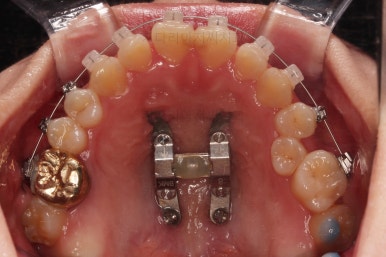

윗니는 가지런하게 하는 동안 아랫니는 중앙선을 개선하기 위해 미니스크류를 이용해 뒤로, 뒤로 계속 당겨주게 됩니다.

힘 조절도 적절히 해가면서 아래 치열을 뒤로뒤로 옆으로 옆으로 밀어줍니다.

만족스러운 수준까지 정중선을 개선하고 교합도 개선한 뒤, 마무리를 해줍니다.

정중선을 개선하는게 참 오래 걸리는 치료이기는 해서 26개월이라는 부산교정 시간이 걸리긴 했는데요.

교합, 중앙선 등 모든게 많이 좋아진 만족스러운 치료였습니다.